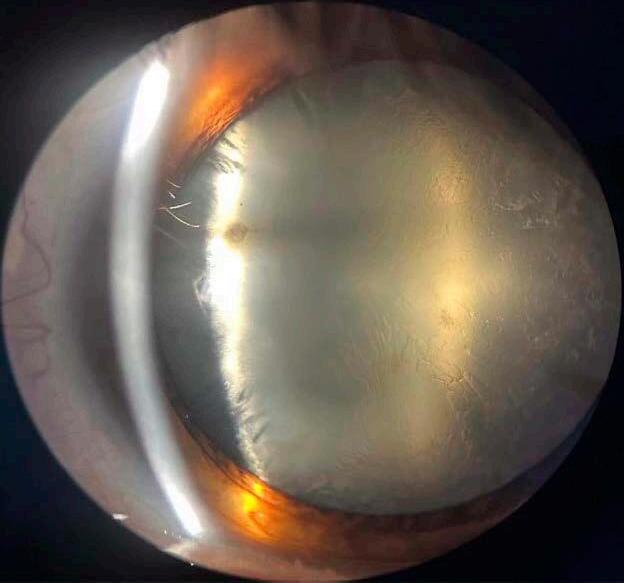

7. Casos desafiantes y estrategias adaptativas

Veremos a continuación ejemplos prácticos, ya que una cosa es elegir la lente perfecta en una cirugía estándar y otra muy distinta es decidir en el “campo de batalla” cuando la bolsa capsular se rompe, la zonulación se debilita o un paciente llega con múltiples antecedentes quirúrgicos. Es ahí donde la tecnología debe ceder espacio al criterio quirúrgico y la planificación se transforma en adaptación.

Revisión narrativa sobre lentes intraoculares en evolución: de la precisión óptica a la experiencia visual personalizada.

7.a La pseudoexfoliación capsular: la fragilidad como constante

Uno de los escenarios que más respeto me genera —y que más frecuentemente encuentro en la práctica diaria— es el de la pseudofoliación, como la literatura científica también lo ha demostrado. 44,45 Cápsulas que parecen estables pero colapsan al menor movimiento, zonulólisis subestimadas en las imágenes preoperatorias, y pupilas rígidas que complican cada paso.

En estos casos, prefiero anticiparme. Si la sospecha es alta, elijo lentes con buena estabilidad háptica, evito implantes premium complejos y tengo siempre listo un anillo de tensión capsular. Me ha tocado, más de una vez, modificar la estrategia intraoperatoriamente, eligiendo una lente monofocal en sulcus con óptica capture para asegurar centrado y funcionalidad.

7.b Rotura capsular: del susto al rescate ordenado

Si bien hay una vasta recopilac ión de información y evidencias acerca de factores que pueden predisponer una ruptura capsular, como también de posibles soluciones intraquirúrgicas ante la aparición de la complicación, 46-48 creo que un interesante aporte es compartir experiencias: en una cirugía reciente, un paciente con alta miopía y cápsula muy elástica terminó con una dehiscencia posterior en la fase final del faco. La lente planificada era una EDOF tórica. Ante la situación, utilicé una técnica mixta: realicé una captura óptica con una lente de 3 piezas, utilizando los restos del borde anterior como soporte, y logré un centrado perfecto. Ese caso, como tantos otros, me recuerda que la tecnología es útil, pero la técnica salva cirugías.

8. Nuevas fronteras: lentes ajustables, ópticas líquidas y plataformas inteligentes

Vivimos una época donde la frontera entre lo posible y lo clínicamente viable se vuelve cada vez más difusa. La investigación y desarrollo en lentes intraoculares ha entrado en una fase de disrupción tecnológica, donde conceptos como ajuste postoperatorio, biomateriales activos y procesamiento inteligente de luz ya no pertenecen solo a los papers, sino que comienzan a asomar en la práctica clínica, como veremos en algunos ejemplos a continuación.

8.a Lentes ajustables con luz: precisión postoperatoria real

Las Light-Adjustable Lenses (LAL) representan uno de los avances más concretos en esta nueva era. 50,51 Su promesa es contundente: corregir hasta el último decimal refractivo después de la cirugía, mediante luz ultravioleta. Esto permite modificar el poder de la lente una vez que el ojo ha cicatrizado, algo impensado hace solo unos años.

Aunque aún no están disponibles en todos los países y su implementación requiere equipamie nto especializado y protocolos estrictos de fotoprotección, son una ventana al futuro de la cirugía refractiva intraocular. En pacientes con antecedentes de cirugía refractiva o topografía s impredecibles, la posibilidad de refinar el resultado posoperatorio con tanta precisión abre un escenario completamente nuevo. 51

8.b Ópticas líquidas y lentes biomiméticas

7.c Ojos previamente operados: topografía difícil, expectativas altas

Otro desafío frecuente son los ojos con cirugía refractiva previa, donde las fórmulas tradicionales pierden eficacia y el cálculo de la LIO casi “se convierte en una apuesta”. En mi caso, para realizar el cálculo de la lente, recurro a múltiples plataformas biométricas, comparo predicciones y busco consenso entre ellas. Es real que el margen de error es mayor y que hay que manejar con el paciente las expectativas de entrada, explicándole de antemano las características “difíciles” de sus ojos.

Otro campo prometedor es el de las ópticas líquidas: lentes que pueden modificar su forma o su índice de refracción mediante estímulos internos o externos y que además incluso pueden incorporar y liberar fármacos co n diversas func iones dentro del ojo. 52 Aunque todavía en etapas de experimentación, estas tecnologías buscan emular la acomodación natural, un objetivo que ha sido el “Santo Grial” de la oftalmología moderna.

En lente, platafor hay expectativas veces una

En paralelo, se investigan lentes con memorias adaptativas, 52 que responden a cambios de temperatura, presión o medios químicos intraoculares, para ajustar su comportamiento óptico según el entorno del ojo. Son materiales “inteligentes” que integran la lógica de la bioingeniería con la necesidad quirúrgica.

8.c Plataformas inteligentes y personalización total

En lo personal a veces elijo una EDOF no tórica en lugar de una trifocal para ganar tolerancia. O incluso una monofocal segmentada, si el ojo tiene cicatrices corneales o aberraciones elevadas. En estos contextos, la tecnología ayuda y aunque es cierto que también existen lentes diseñadas más específicamente para casos difíciles como estos, que tienen una óptica estenopeica,49 lo relevante para el cirujano está en saber cuándo adaptarse, cuándo simp lificar y cuándo renunciar a lo ideal para garantizar lo seguro.

específica mente tienen

La inteligencia artificial y el big data clínico ya se están integrando a los cálculos de LIOs. 54 Plataformas que cruzan millones de datos biométricos, curvas de desenfoque y experiencias quirúrgicas previas para predecir el resultado más probable, adaptado a cada paciente.

INFORME ESPECIAL

Aunque aún estamos lejos de una “lente personalizada” impresa bajo demanda para cada ojo —como promete la bioimpresión 3D—, el concepto de personalización total ya está en marcha: no solo en el diseño óptico, sino en la predicción de adaptación, satisfacción y expectativa visual futura. Mirando hacia adelante, lo que se perfila no es solo una nueva generación de lentes, sino una nueva forma de pensar la cirugía del cristalino: más precisa, más flex ible, más adaptada a cada individuo. Pero también, más exigente para nosotros, los cirujanos, que debemos aprender a dominar tecnologías sin perder de vista lo esencial: el ojo, el paciente, y el acto quirúrgico como encuentro humano.